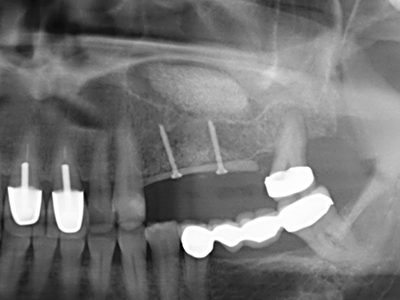

La piezochirurgia presenta altri vantaggi per quanto riguarda la raccolta di blocchi ossei. Oltre all'elevata precisione dell'osteotomia appena descritta, l'utilizzo di puntine per sega molto sottili permette di minimizzare in maniera significativa la perdita di materiale. È molto probabile che si verifichi una maggiore perdita di materiale durante la raccolta utilizzando puntine di strumenti più spessi, in particolare delle frese Lindemann (Lakshmiganthan, Gokulanathan et al. 2012). La separazione basale, necessaria in particolare per i trapianti di blocchi nella zona retromolare, viene semplificata grazie a seghe specificatamente progettate di forma rettangolare; di conseguenza la piezochirurgia è considerata una procedura precisa, semplice e sicura per la raccolta di blocchi di osso nella zona retromolare (Happe 2007) (figg. 1-12).

Indicazione: incisione ossea